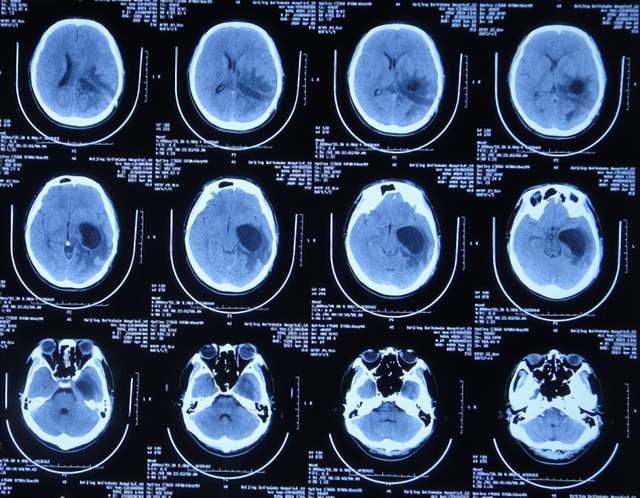

直到2021年1月8日(间断头痛4年后),因无法忍受头痛,就诊于山东省济南市商河某医院,查头颅核磁示颅内占位(图-1)。

图-1:2021年1月8日头颅核磁

为治疗脑瘤,于5天后即2021年1月13日,就诊于山东省某省级三甲医院,查头颅核磁增强(图-2)和头颅血管造影(图-3)示颅内占位。

图-2:2021年1月13日头颅核磁增强

图-3:2021年1月13日头颅血管造影

入院后5天即2021年1月18日,查头颅CT增强示颅内占位(图-4)。

图-4:2021年1月18日头颅CT增强